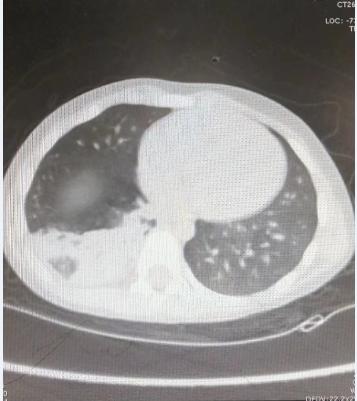

治疗前肺CT

最近,3岁的奇奇(化名)宝宝因发热、咳嗽口服了不少药,但咳嗽始终不减轻、且仍伴有发热症状。家长急忙带着孩子来到山东省立三院儿科就诊。“当时医生说肺里痰鸣音特别多,喘鸣音也很明显,肺CT提示右肺下叶局部实变,诊断为重症肺炎”,奇奇妈妈回忆说。